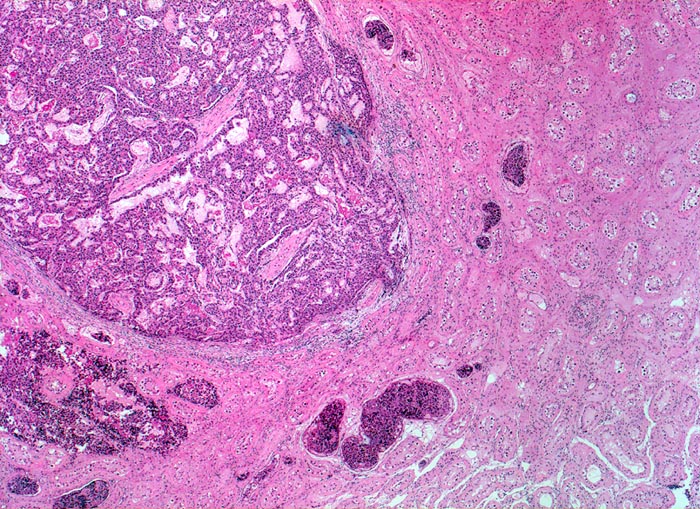

Embryonales Karzinom des Hodens

Das Karzinom wächst teils expansiv, teils infiltrativ. Es sind mehrere Gefässeinbrüche nachweisbar. In den Hodentubuli hat es atypische vergrösserte Keimzellen entsprechend einer testikulären intraepithelialen Neoplasie. Die in situ Komponente zeigt teilweise dieselbe Differenzierung wie das embryonale Karzinom und weitet die Tubuli aus.

Makroskopisch aus mehreren unscharf begrenzten, bunten, teils hämorrhagischen Knoten bestehender Tumor von 3cm Durchmesser.

Das Vorliegen von Spaltartefakten zwischen Tumorzellen und tubulärer Basalmembran bei einer testikulären intratubulären Neoplasie kann fälschlicherweise den Eindruck einer Gefässinvasion erwecken. Eine Gefässinvasion kann nur dann diagnostiziert werden, wenn die tubuläre Struktur eindeutig von Endothelzellen ausgekleidet wird.